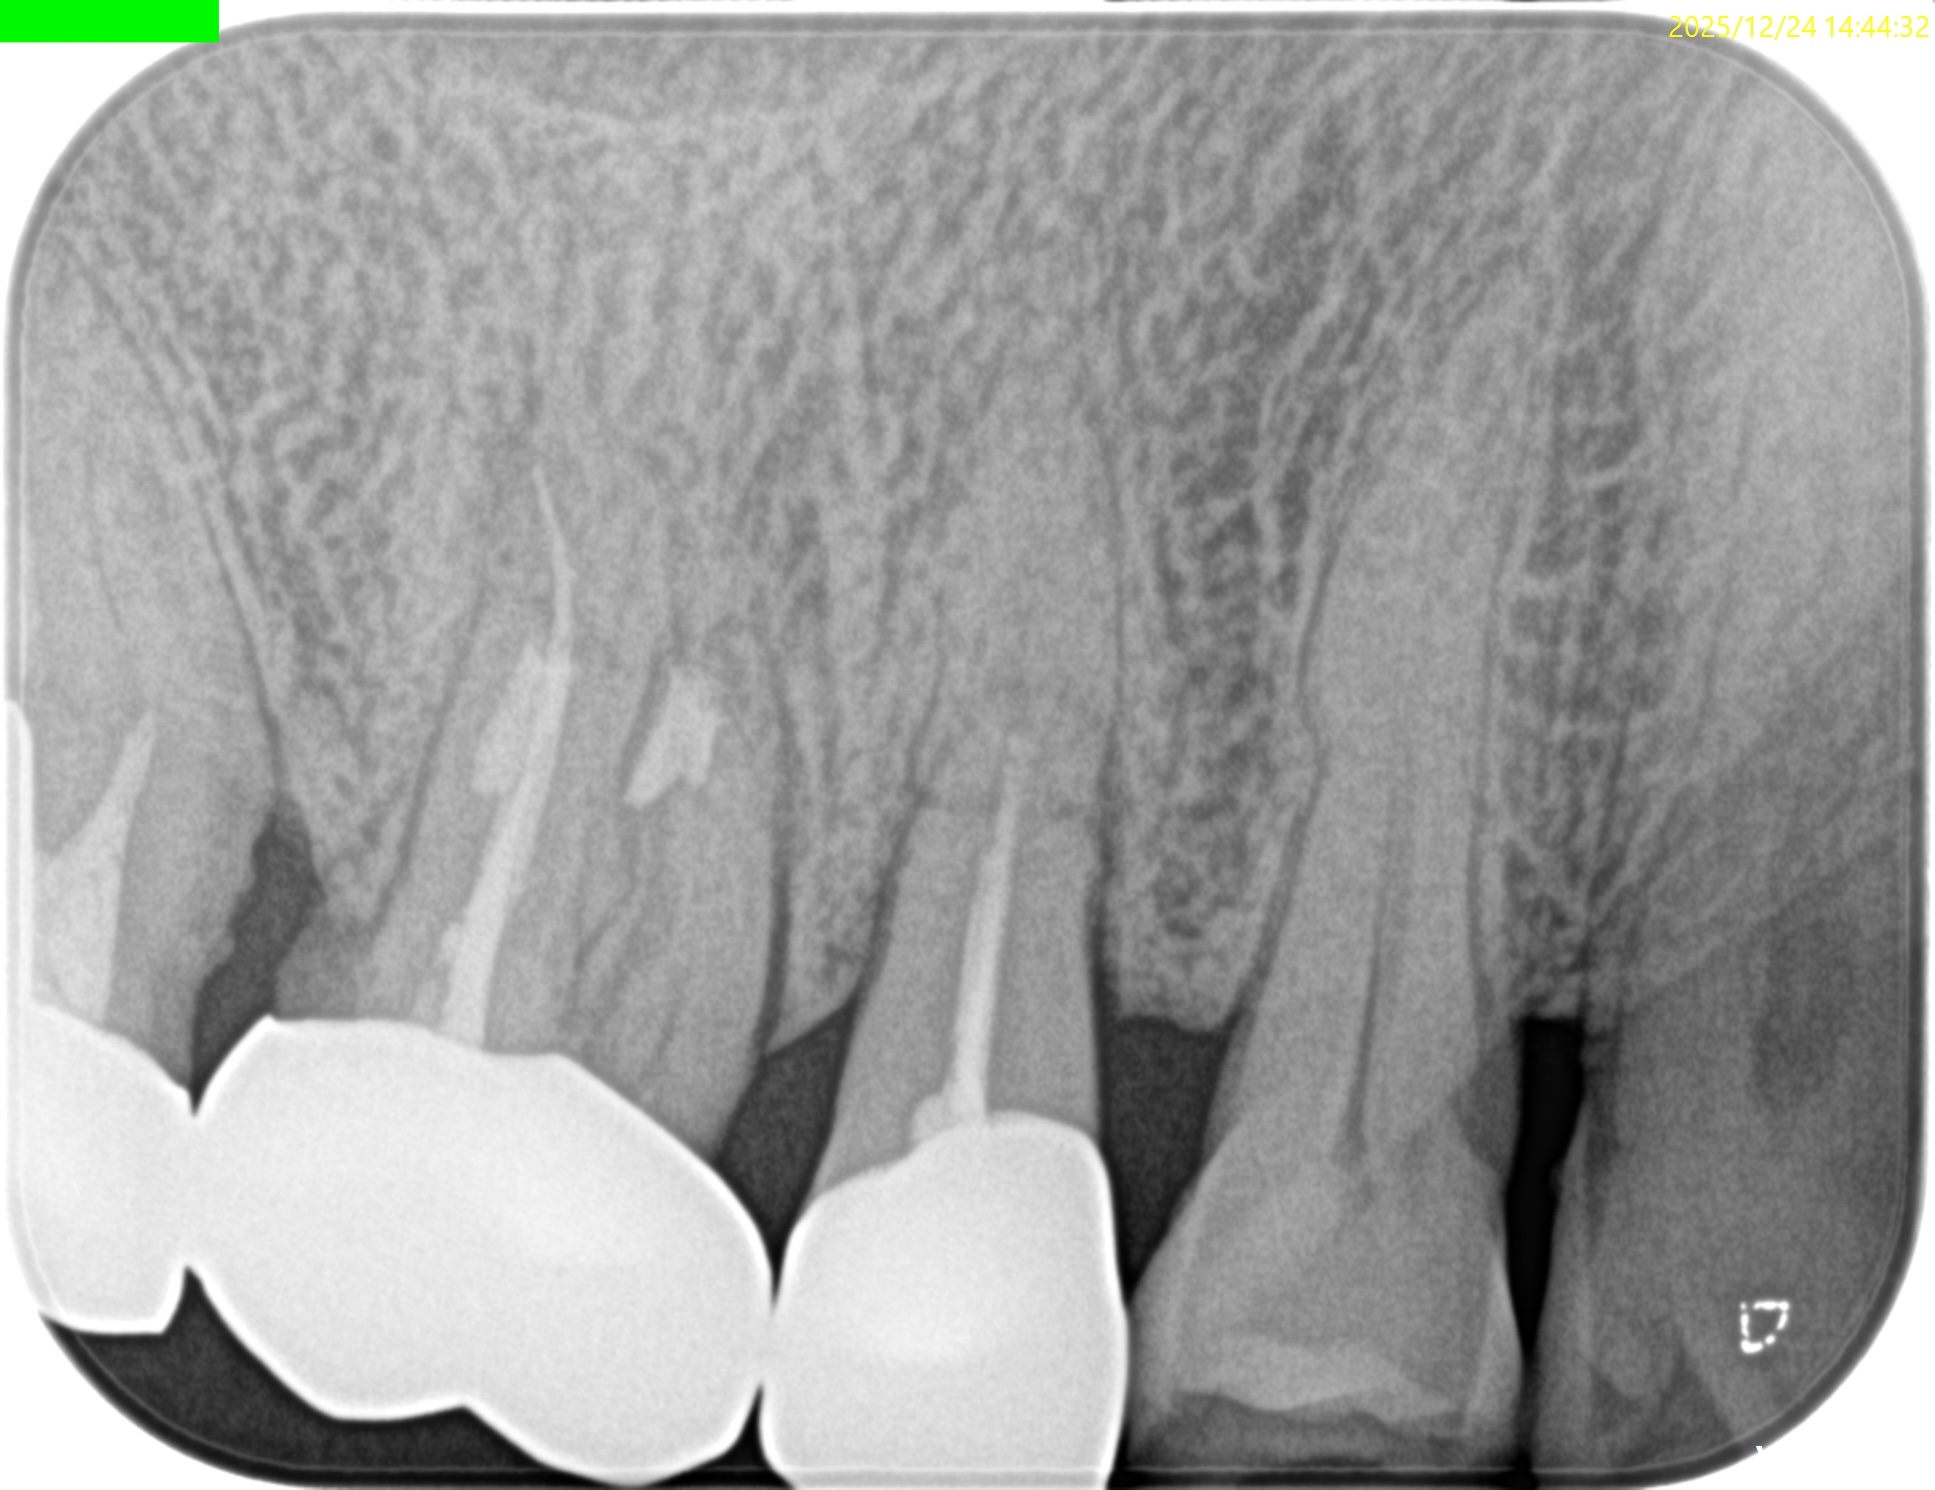

#3 MB,DB Apicoectomy 1yr recall(2025.12.24)

術前のSinus tract・臨床症状(根尖部圧痛)も術後の縫合の傷跡もない。

MB

DB

B

外科治療の際に開創した歯槽骨は再生した。

術前と比較した。

問題は消失した。

MBは根尖部の形成は穿孔しているだろうが即座に穿孔封鎖したから=即座に逆根充したから問題が起きていない。

ということで完治したのでこの日で終診とさせていただいた。